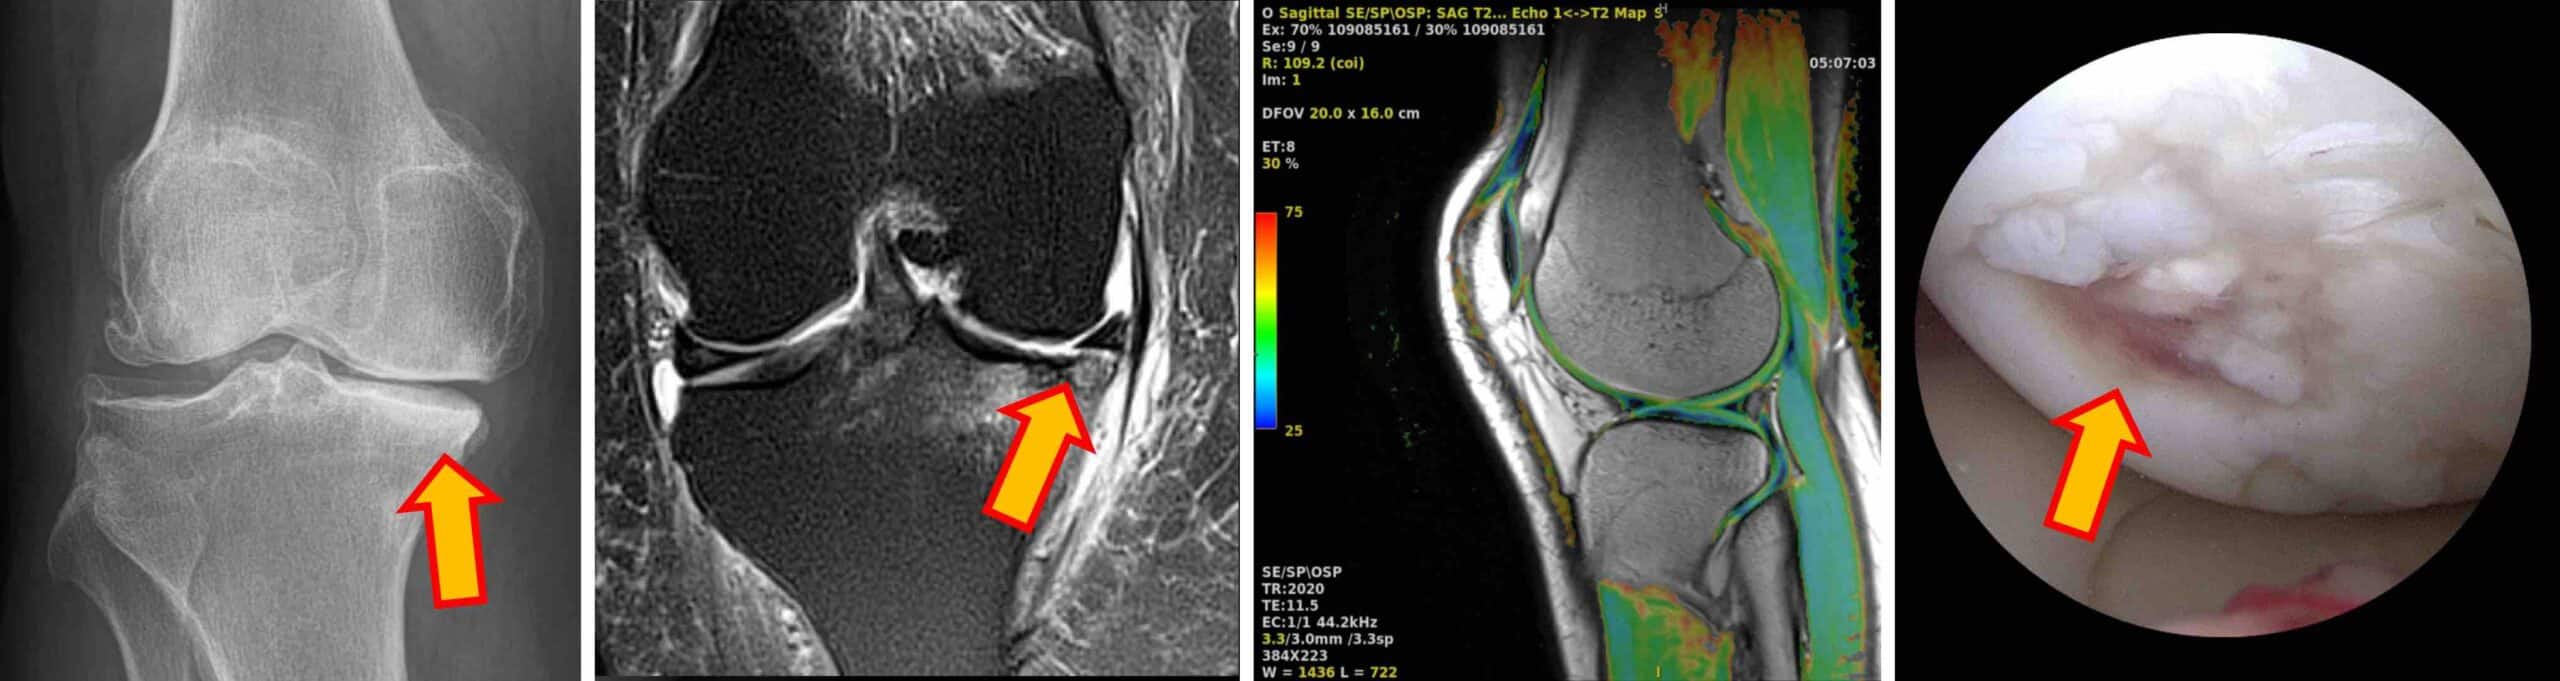

O diagnóstico das lesões e doenças envolvendo a cartilagem do joelho é feito pela história clínica completa, exame físico do joelho e exames complementares. RX é útil para observar o alinhamento articular e sinais de artrose. A ressonância magnética é o melhor exame de imagem para identificar as alterações na cartilagem, outras lesões associadas e inflamações. A artroscopia diagnóstica também permite o diagnóstico das alterações da cartilagem e pode ser indicada para pacientes que não podem ser submetidos ao exame de ressonância magnética.